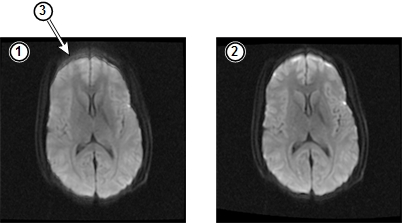

The following illustration shows the effects of these high order eddy currents and the results of HOEC correction. (The images have been adjusted to make the defect more apparent.)

| 1 | Uncorrected SSE image | 2 | HOEC corrected SSE image |

| 3 | Blurring related to mis-registration due to high order eddy currents |